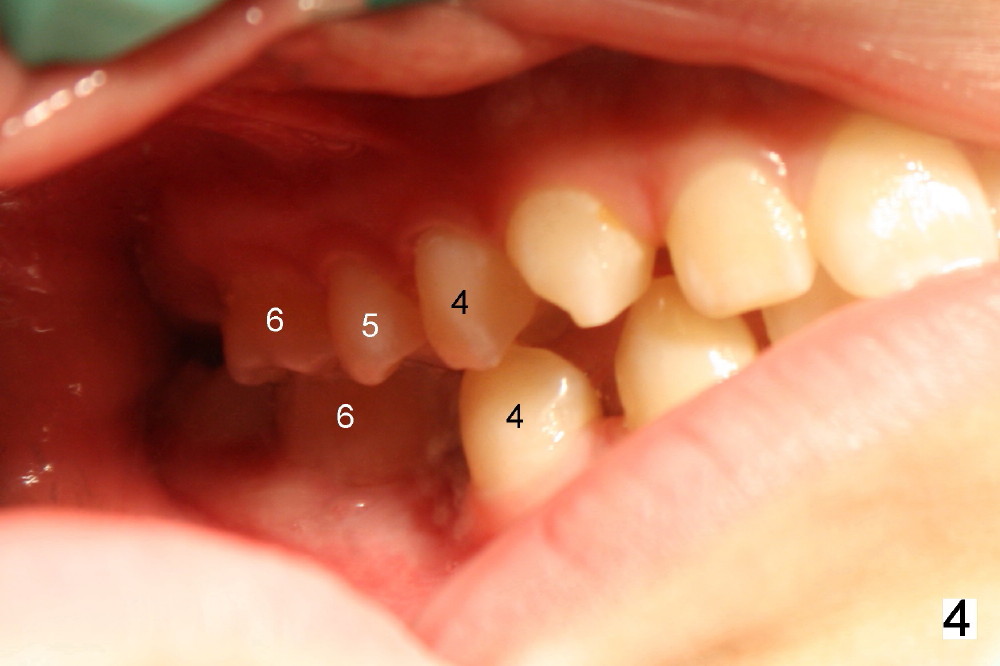

Two lower 2nd bicuspids are congenitally missing in a 11-year-old boy (Fig.1).  The lower left  (LL) E has been extracted due to caries.  There is severe periapical radiolucency associated with the LL6.  Root canal therapy (RCT) is being carried out for this molar with difficulty.  In addition, the boy is a dental phobic, refusing to have the lower right E extracted in spite of DO caries and pain.  In order to reduce the chance of future surgery, including extraction, there are two orthodontic plans to move the lower molars mesially.  Fig.2-4 show that the anterior occlusion and right posterior interdigitation is nearly within normal limit, whereas the left is not.